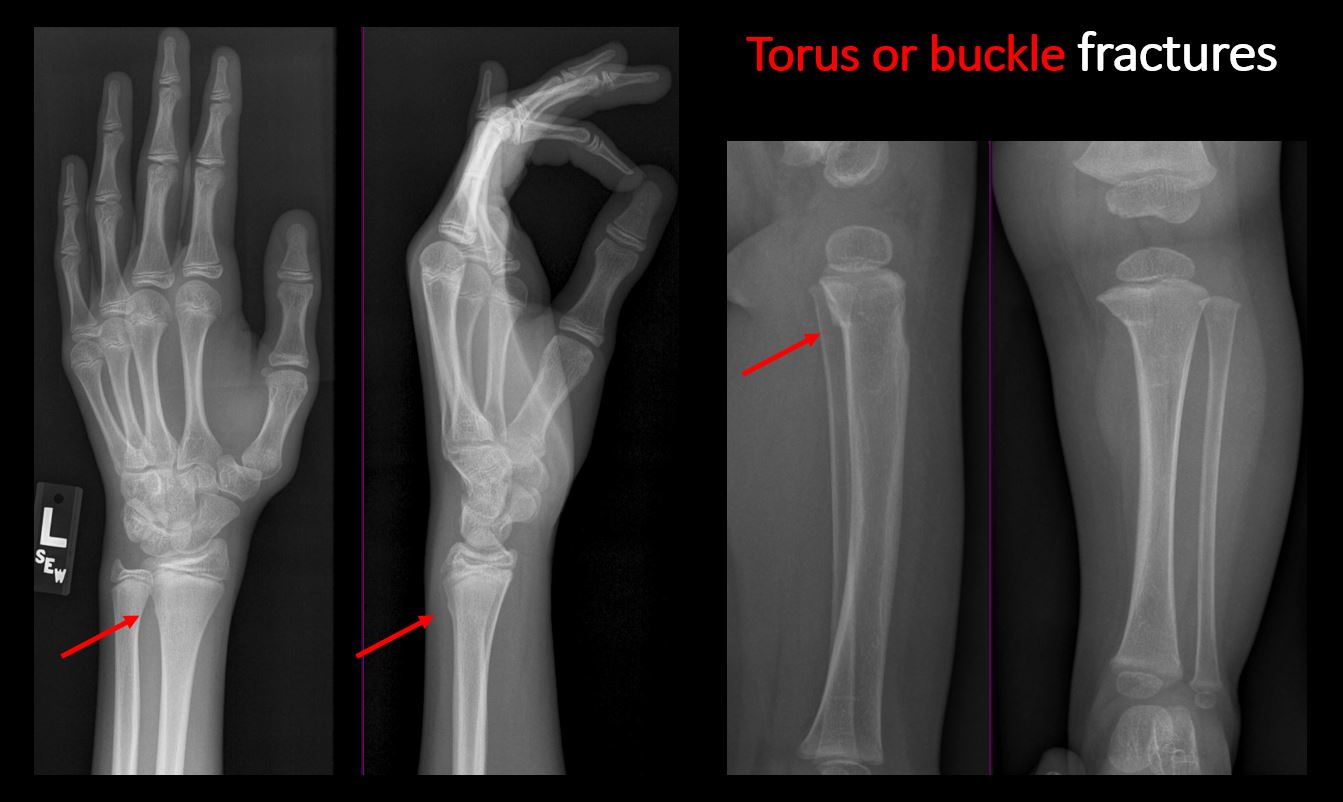

There is abnormal angulation or bulging of the cortical surface relative to the normal cortex which could be from a buckle or torus fracture. [Yes/No]